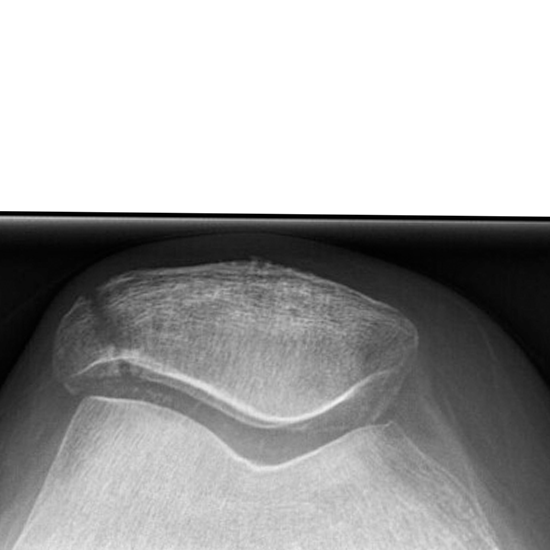

X-Ray Knee Skyline View

The skyline or axial view of the patella-femoral joint shows valuable information about its shape and anatomy. It gets a piece of the patella's axial projection (kneecap). It works well for patients who can stay in a semi-reclined (half-lying down) position on the exam table.

• This view is used in trauma and orthopedics to check for patellar fractures or subluxations and patellofemoral joint disease.

• To identify infections, osteoporosis, bone abnormalities, or abnormal bone development.

• To diagnose dislocation of the knee.